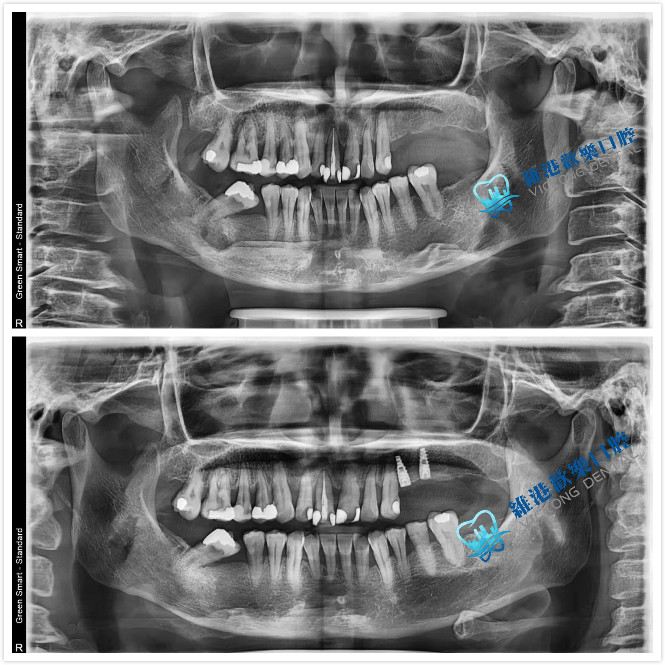

案例分享:

深圳維港歡樂口腔-陳培章醫生拔除阻生智慧齒